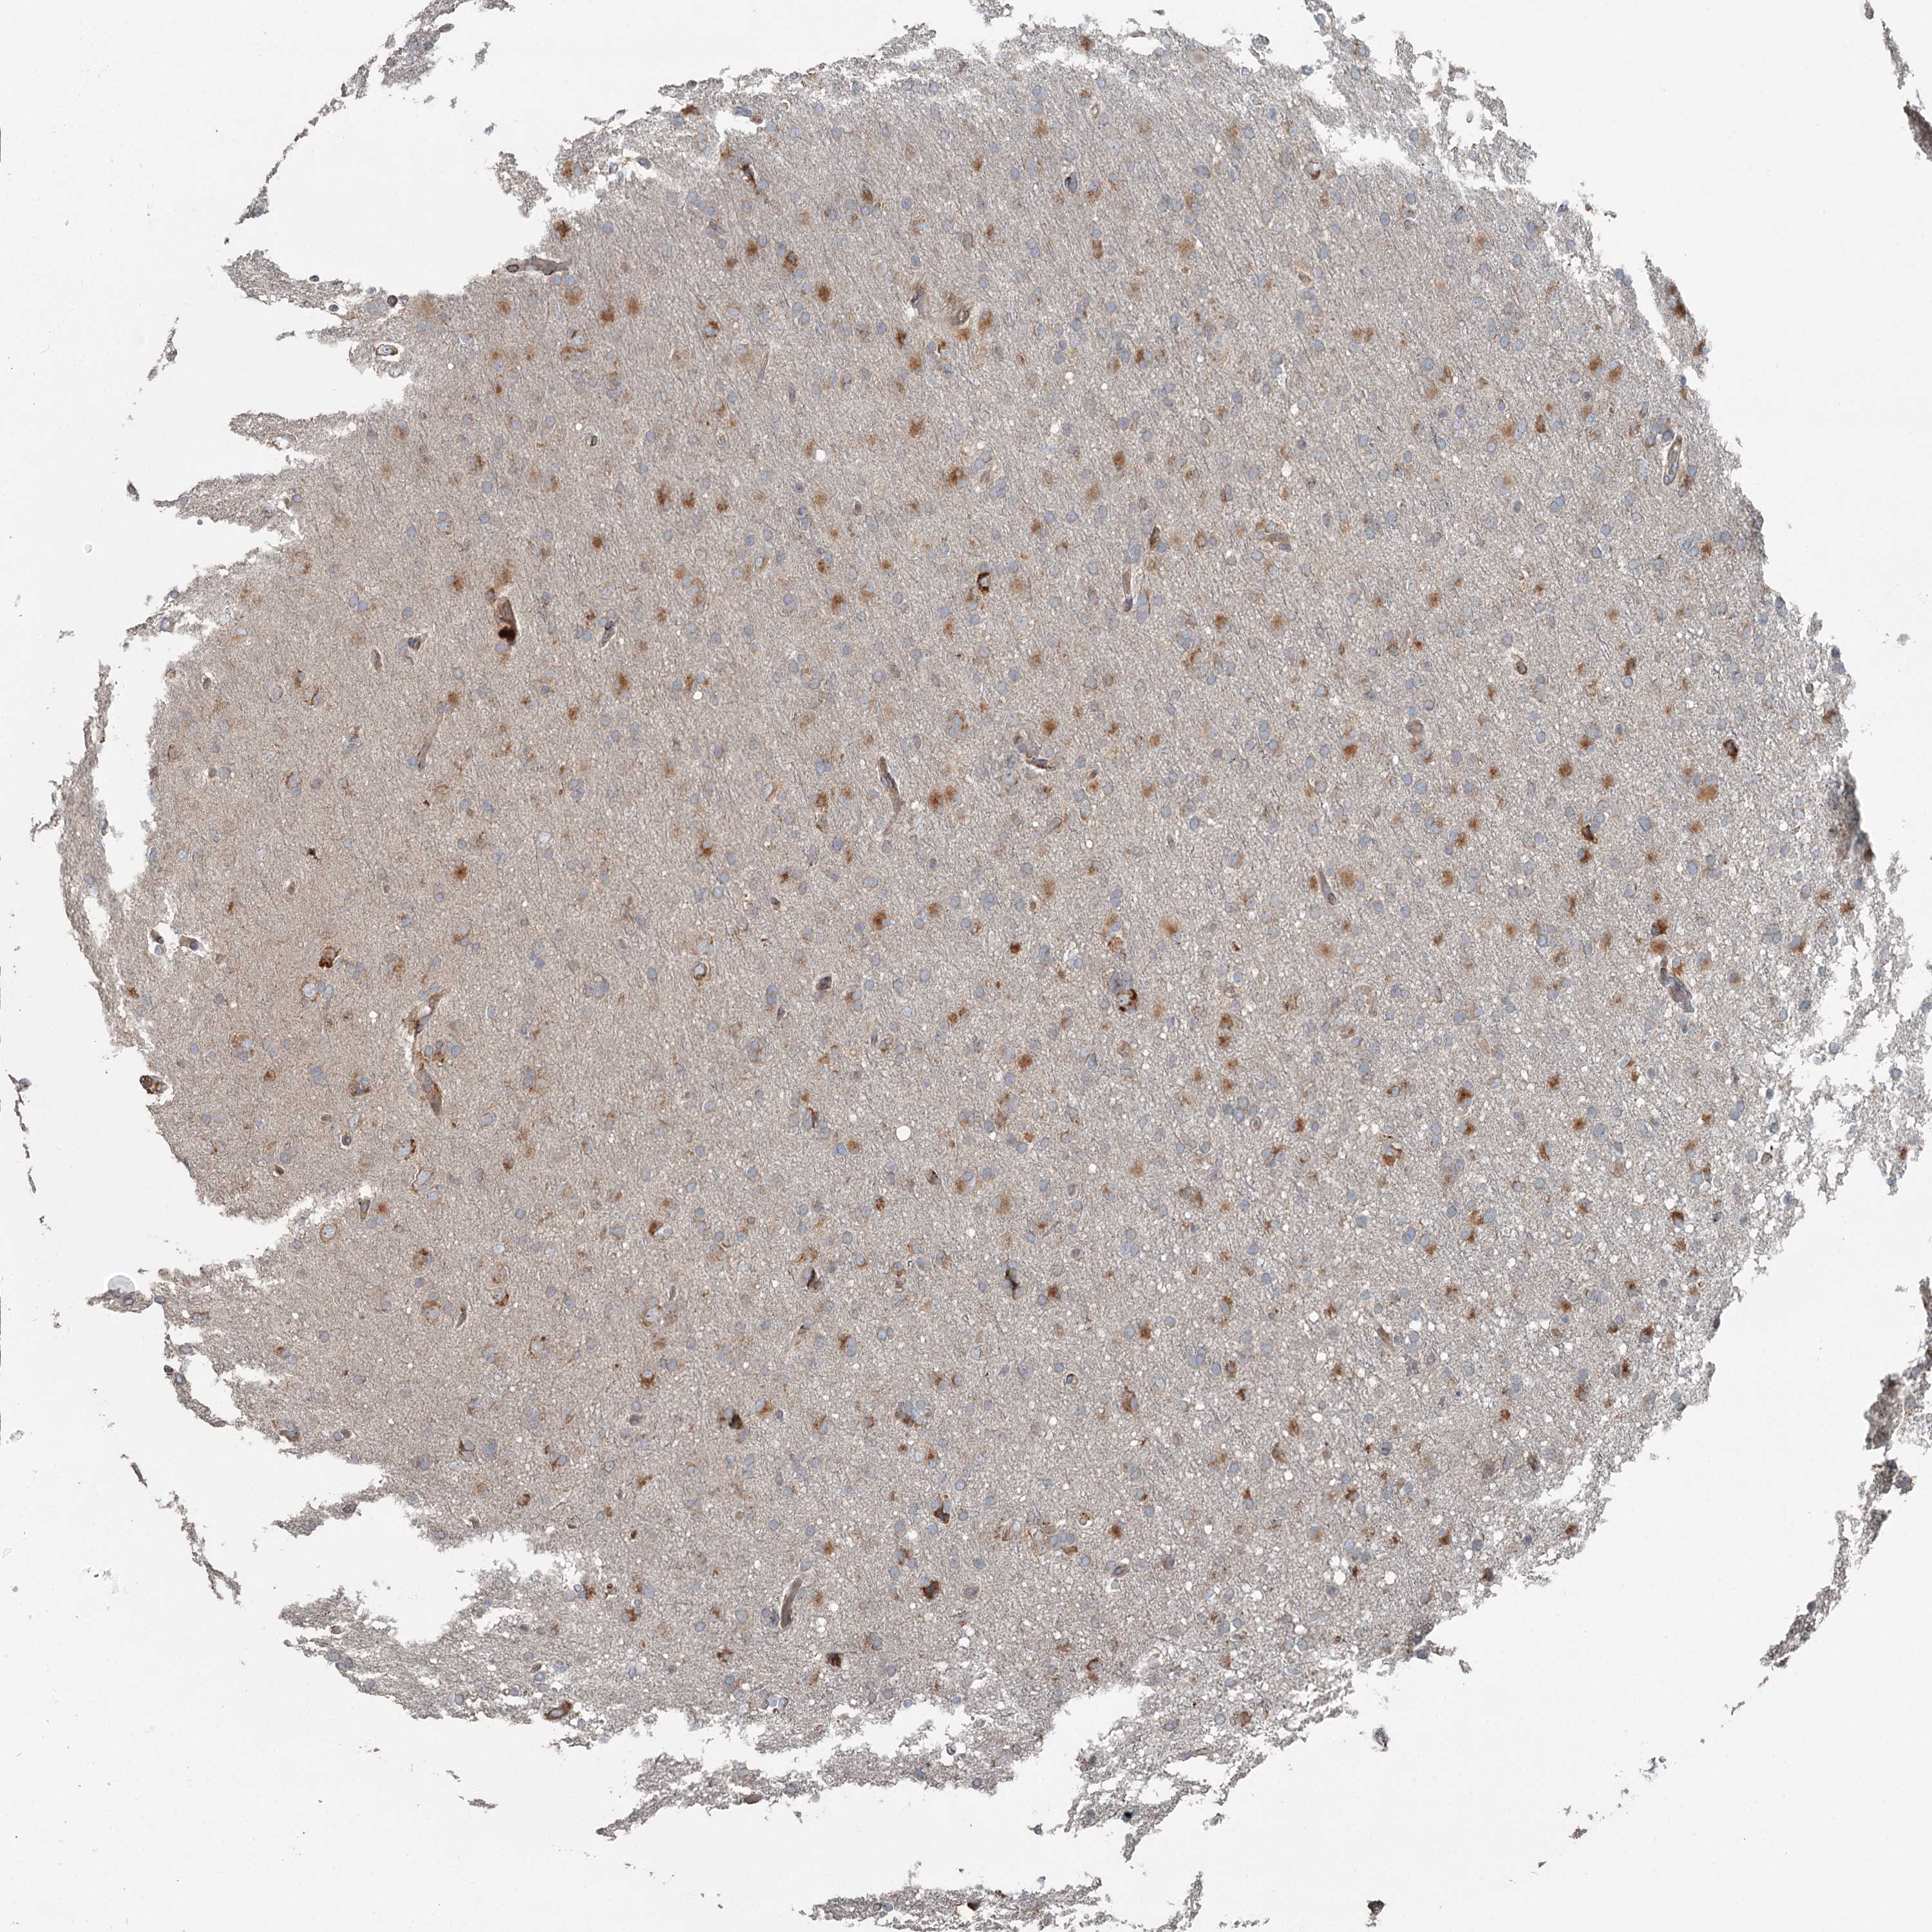

GLIOMA - Protein expressioni

A mouse-over function shows sample information and annotation data. Click on an image to view it in a full screen mode. Samples can be filtered based on level of antibody staining by selecting one or several of the following categories: high, medium, low and not detected. The assay and annotation is described here.

Note that samples used for immunohistochemistry by the Human Protein Atlas do not correspond to samples in the TCGA dataset.

Antibody stainingi

Antibody staining in the annotated cell types in the current human tissue is reported as not detected, low, medium, or high, based on conventional immunohistochemistry profiling in selected tissues. This score is based on the combination of the staining intensity and fraction of stained cells.

Each image is clickable and will lead to virtual microscopy that enables deeper exploration of all samples and also displays staining intensity scores, fraction scores and subcellular localization as well as patient and tissue information for each sample.

Antibody HPA038163

Antibody HPA038164

Staining

High

Medium

Low

Not detected

Intensity

Strong

Moderate

Weak

Negative

Quantity

>75%

75%-25%

<25%

None

Location

Nuclear

Cytoplasmic/membranous

Cytoplasmic/membranous,nuclear

Glioma, malignant, High grade

Glioma, malignant, Low grade

Glioblastoma, NOS